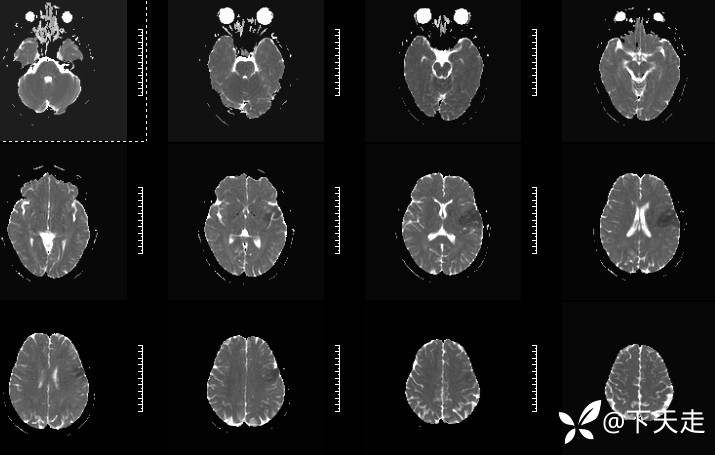

青鹊词 推荐青年女性,37岁,因不能言语就诊于耳鼻喉科,耳鼻喉科医生诊疗后建议神经内科就诊。

查体:神清,完全性运动性失语,四肢肌张力正常,肌力5级。

相关检验检查资料如下